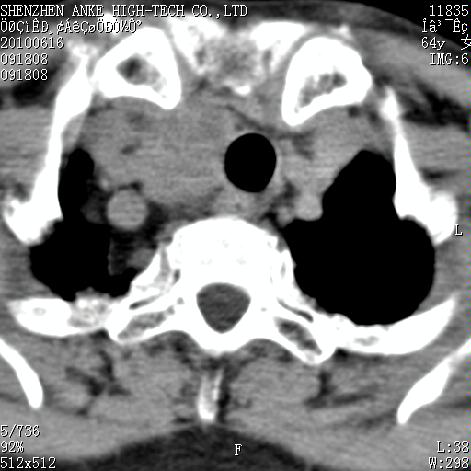

标题: CT27132:患者女,64岁,颈部及全身多处包块,现觉吞咽困难4 [打印本页]

标题: CT27132:患者女,64岁,颈部及全身多处包块,现觉吞咽困难4

右侧甲状腺占位,肿瘤可能性大,癌

右侧甲状腺癌伴右颌下腺淋巴结转移

右侧甲状腺癌伴淋巴结转移

右侧甲状腺癌伴淋巴结转移可能性大

右侧甲状腺癌伴淋巴结转移可能性大。